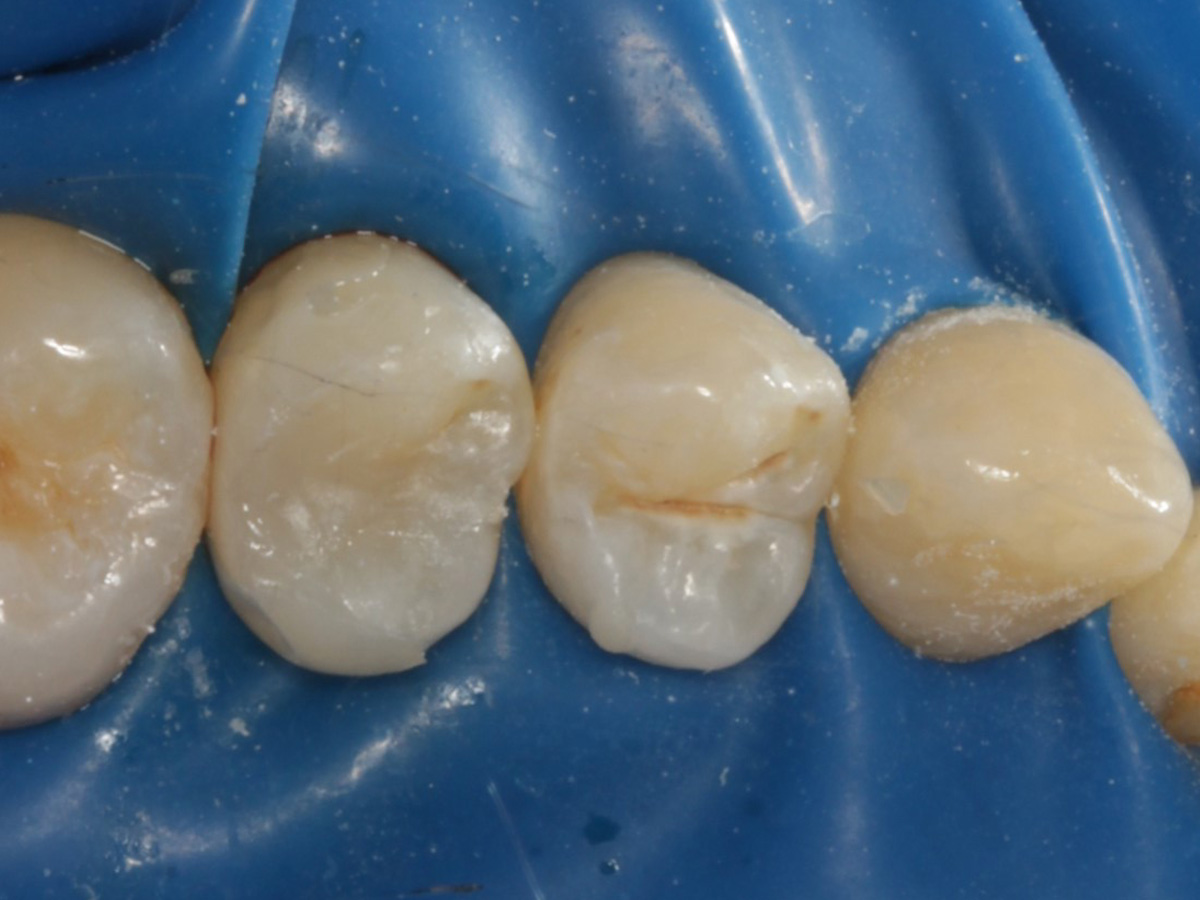

Abbildung 5

Defektdarstellung